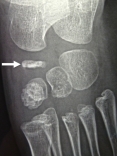

Exemple d'ostéochondrite de l'os scaphoïde (naviculaire) chez un garçon de 5 ans:

Les deux photos de gauche montrent un os densifié et aplati sur le pied gauche.

Les deux photos de droite montrent les mêmes radios sur le pied droit sain.